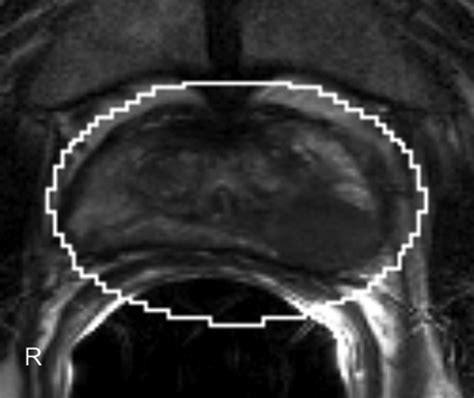

• Multiparametric MRI (mpMRI): This technique combines multiple MRI sequences, including T2-weighted imaging, diffusion-weighted imaging (DWI), and dynamic contrast-enhanced (DCE) imaging, to provide a comprehensive evaluation of the prostate.

• Prostate Imaging Reporting and Data System (PI-RADS): This standardized reporting system helps radiologists interpret MRI findings and classify the likelihood of clinically significant prostate cancer.